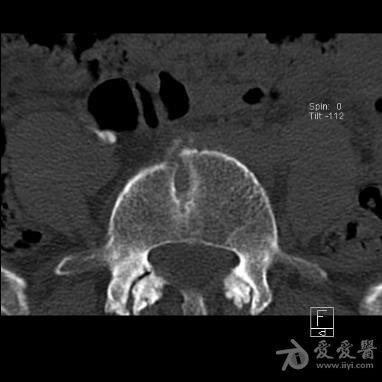

蝴蝶椎(ct) - 医学影像学讨论版 - 爱爱医医学论坛